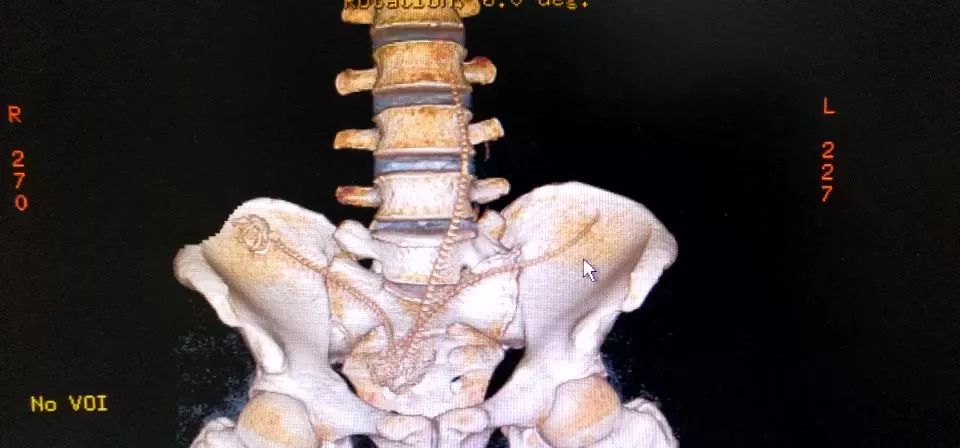

CT三维重建下三条泥鳅的骨骼清晰可见

占据整个下腹部和盆腔......

2月10日那天我看的急诊,事情的经过是这样的,我是他的首诊大夫,一开始急诊打电话急会诊说是吃泥鳅吃坏了肚子,我觉得这也没啥,然后让他做腹部CT。后来看到他的CT赫然三条鱼骨头。我一看CT很吃惊,难道是生吃的?

去一楼急诊问患者本人,当时我听他说了事实,是下面塞进去的真把我吓一跳。他第一句话就是说,听信网上前列腺偏方把他害惨了,让我救救他赶紧手术,问我有没有穿孔,当时只有一个小时,还早,摸着板状腹很硬。他意识还有,后来就慢慢感染中毒休克了。后来术中发现乙状结肠穿孔,三条鱼都到了腹腔里,有一条还往回盲部钻,不过取出来应该都是死的了。